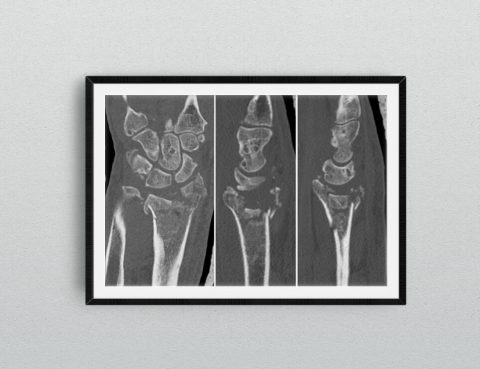

Un algoritmo sul trattamento della Rizoartrosi. Uno strumento utile ai chirurghi e al paziente.